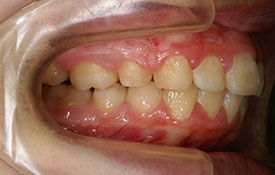

インビザラインの治療例:CASE-1

| プロフィール | 42歳 女性 |

| 所見 | 他院で行われた矯正歯科治療後の後戻りに悩まれて来院されました。 アイライナーの装着は、1日平均20時間ほどでした。 |